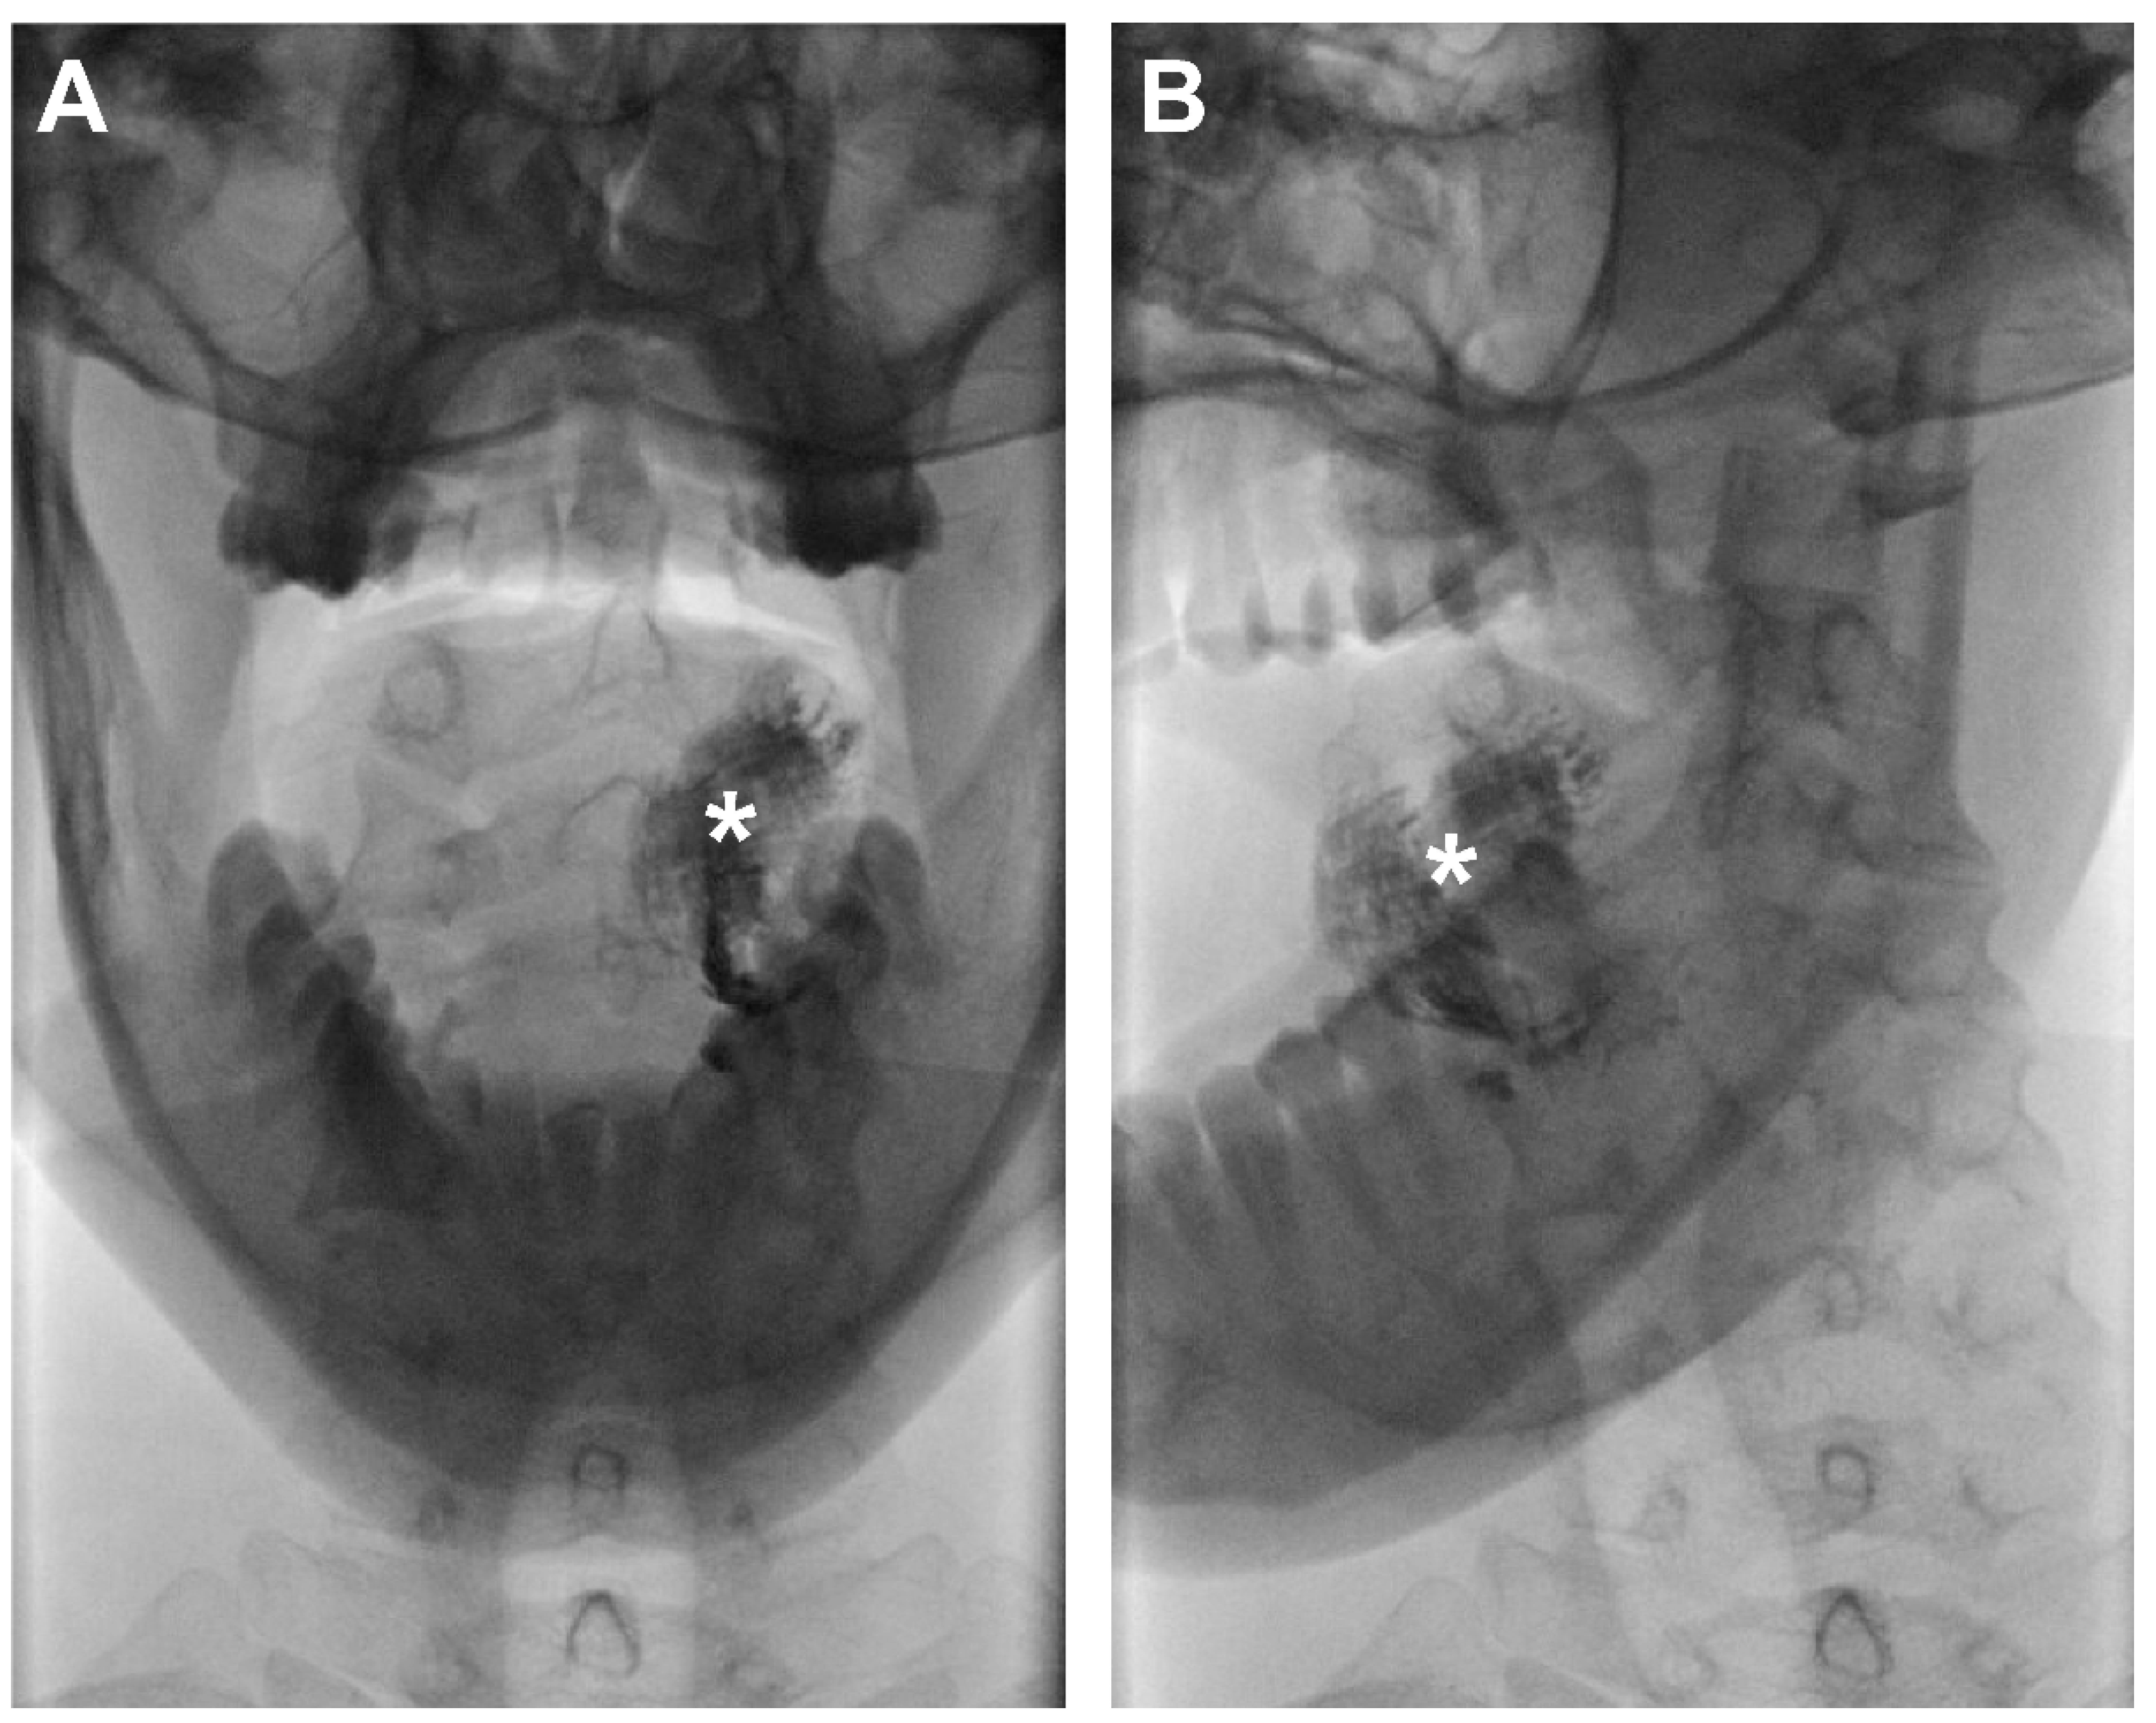

Figure 2.

Contrast-inverted dynamic X-ray images acquired 10 min following peritumoral injection of Lipiodol® in a patient with cT1N0 OSCC on the left side of the oral tongue (patient 6). No lymphatic drainage of Lipiodol® was observed with dynamic X-ray. (A) Anterior–posterior odontoid projection; (B) anterior–oblique odontoid projection; (*) injection site.